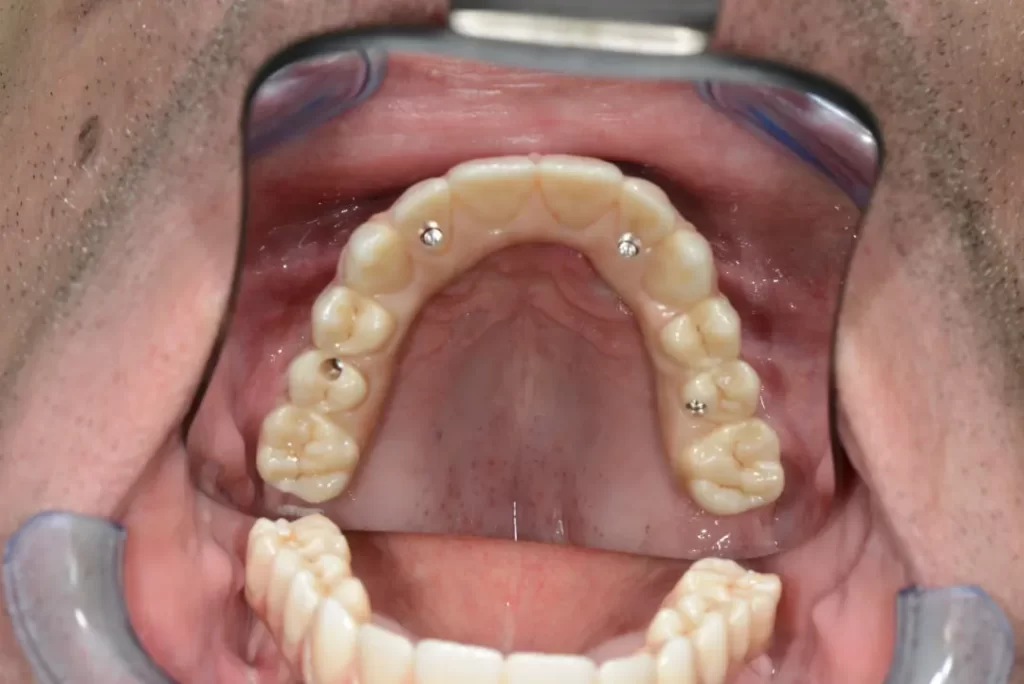

По отношение на протезирането /зъбите върху зъбните импланти/ е необходимо отворите през които преминават закрепващите винтове да се разположат в централната фисура на зъбите. Това се постига чрез т.н. Multy unit. При имплантите Nobel speedy в горната част има външен хексагон. На него се закрепва multy unit във възможните 18 позиции. Това дава голяма възможност на зъболекаря, така да позиционира multy unit спрямо импланта, че отворите по дъвкателната повърхност на зъбите, да са точно в дъвкателния улей. За сравнение, при всички други импланти възможните позиции са 6 във вътрешен хексагон. Това означава, че при Nobel speedy вероятността за почно позициониране е три пъти по-голяма. Тази точност може да се окаже решаваща за крайното лечение по метода All on 4.

При вътрешният хексагон фиксирането на временната конструкция към имплантите е значително по-рисково и би могло да създаде неприятни проблеми, отколкото при външния хексагон на зъбните импланти Noble speedy.